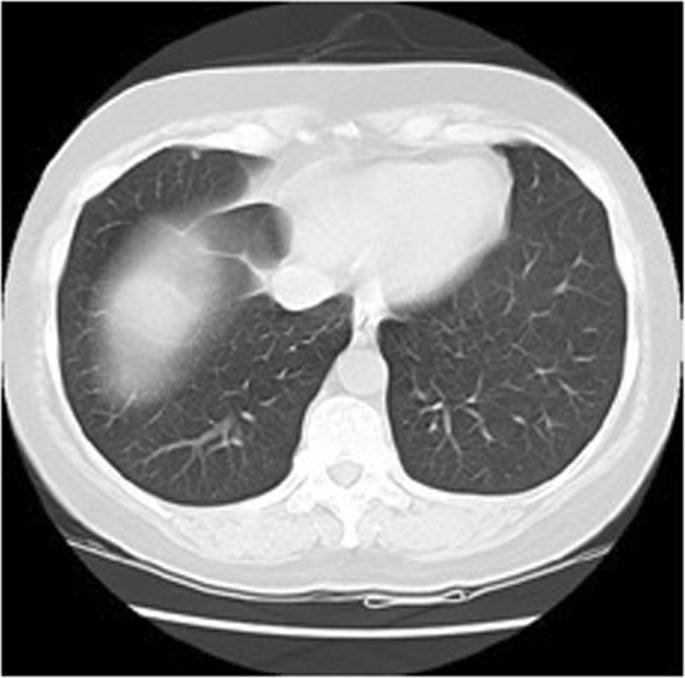

Partial Volume Effect - CANCER PROBE

Partial Volume Effect - CANCER PROBE from sites.google.com